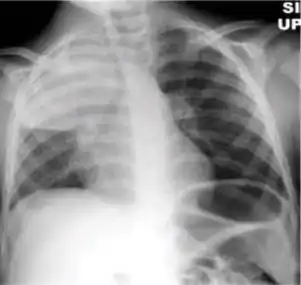

Dense homogenous opacity in right, middle and lower lobe of primary pulmonary TB.

Chest x-ray showing patchy opacification on the upper right and mid-zone lung with fibrotic shadows, as well as bilateral hilar lymphadenopathy.